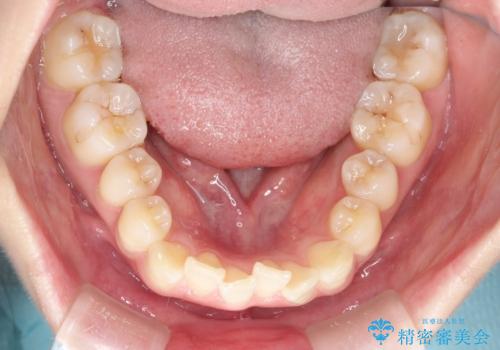

前歯のガタつきをマウスピース矯正で改善

- 前歯のガタツキが気になると来院されました。

奥歯の噛み合わせは綺麗に噛んでいたため、前歯の叢生(でこぼこ)に集中して治療するように計画しました。